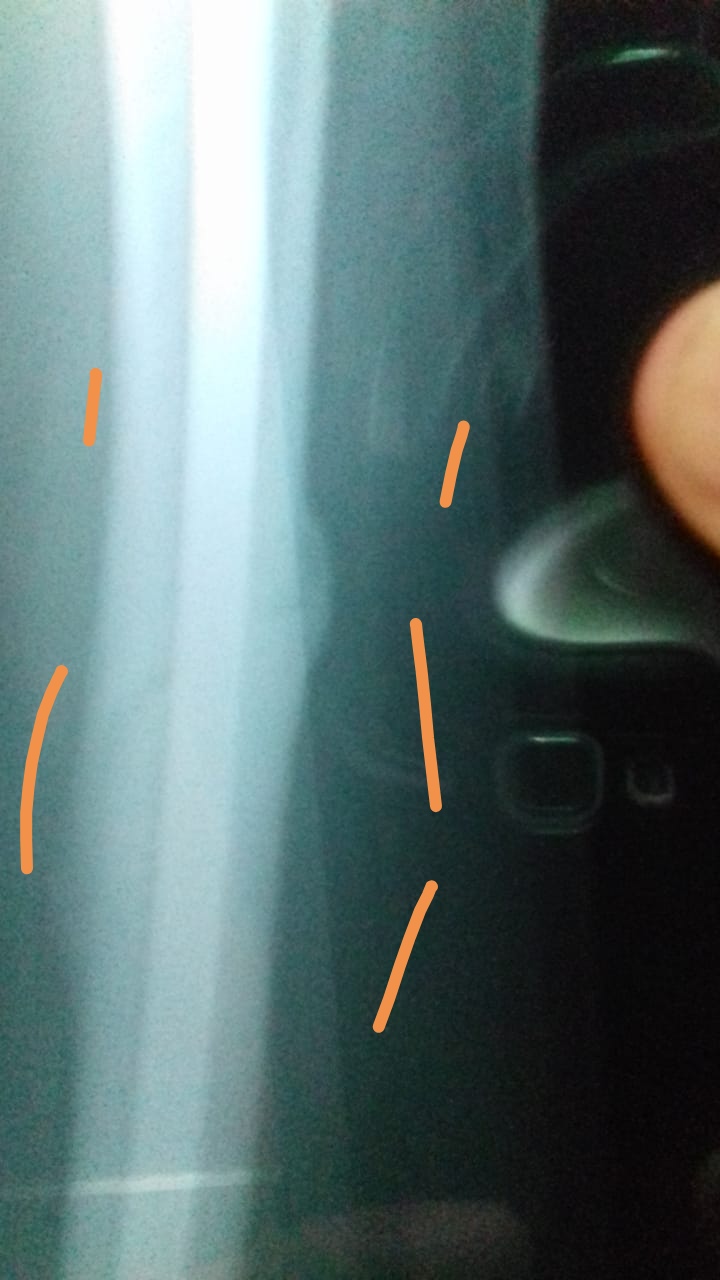

Please tag to an orthopedic surgeon.. My father age 60 had femur shaft fracture in Dec 2019 about 6 months ago where thigh bone has been broken in a angled line as shown in initial attached x ray. Dr. Implanted a rod with support in knee. In first 2 months he suffered from anxiety, but now he just feel uncomfortable in knee when he walk fastly or go up stairs. Now I attached today's x report could you please tell me the stage of healing process? Today one orthopedic surgeon advised that rod need to remove after couple of weeks because this rod is Biger than the usual used for these surgeries. But the surgeon who implanted gave us time period of one year to remove the rod. .should we go for rod removal? rod. I am attaching prescription and x ray in comments.

The nail is bending and the fracture line is visible,it is better to use cruthes while walking and wait for another six months

it's retrograde femur nailing. not a very poor procedure as it can damage knee articular cartilage. the nail is bent and as it seems there is shining callus which is going into consolidation. if weight bearing is painful then use a zimmer frame otherwise no issue. remove the nail after 1 year post op

This is retrograde nail and is done by opening up knee joint... So the distal part sometimes create problem with knee... Its realy to rem9ve the naip, so please avaoid stressea on stairs and squatting postures... Keep in touch with surgeon to get it removed early as the union is achieved fully

rod should be removed after 12 to 18 months ,dont remove it before,size is adequate,thanks